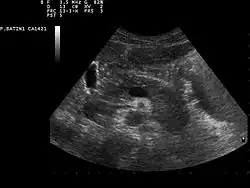

Ultraschallbild der Bauchspeicheldrüse

Zur Erkennung von Tumoren der Bauchspeicheldrüse werden bildgebende Verfahren wie Sonografie, Computertomographie, Magnetresonanztomographie sowie ein kombiniertes endoskopisch-radiologisches Verfahren, die sogenannte Endoskopisch retrograde Cholangiopankreatikographie, genutzt.[51] Darüber hinaus kann mittels Bauchhöhleneröffnung (Laparotomie) und -spiegelung (Laparoskopie) das Organ direkt beurteilt werden. Die Flexible Transgastrische Peritoneoskopie ist ein im Experimentalstadium befindliches Untersuchungsverfahren. Auch Pankreaspseudozysten, Pankreassteine (deren sicherer Nachweis erst nach Einführung der Röntgendiagnostik, etwa durch Arthur Mayo-Robson,[54] möglich wurde) oder Pankreasverkalkungen können mit den genannten bildgebenden Verfahren erkannt werden. Als brauchbarer Tumormarker hat sich CA 19-9 bewährt.[55]